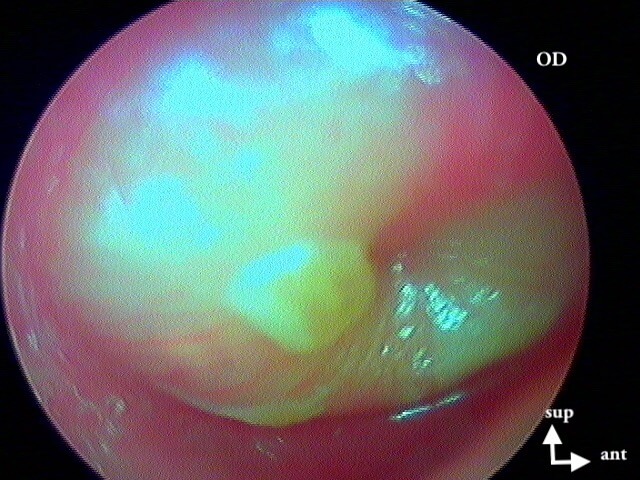

4 OTITE MOYENNE AIGUË (OMA)

Bombement , épanchement rétrotympanique purulent jaune vif, inflammation globale; avec le cas particulier de la myringite bulleuse (virale).

MYRINGITE BULLEUSE VIRALE (chercher la bulle, souvent chez l'adulte, très douloureuse en décubitus, perfore la nuit, otorragie)

Ici une myringite bactérienne ou virale, pas de bulle.